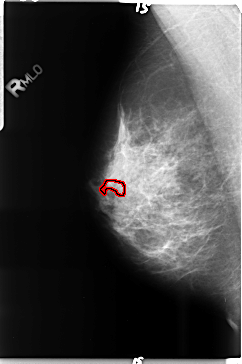

B_3517_1.RIGHT_MLO

RIGHT_MLO LINES 4720 PIXELS_PER_LINE 3136 BITS_PER_PIXEL 12 RESOLUTION 50 OVERLAY

FILE: B_3517_1.RIGHT_MLO.OVERLAY

TOTAL_ABNORMALITIES 1

ABNORMALITY 1

LESION_TYPE CALCIFICATION TYPE PLEOMORPHIC DISTRIBUTION LINEAR

ASSESSMENT 4

SUBTLETY 3

PATHOLOGY MALIGNANT

TOTAL_OUTLINES 1

BOUNDARY